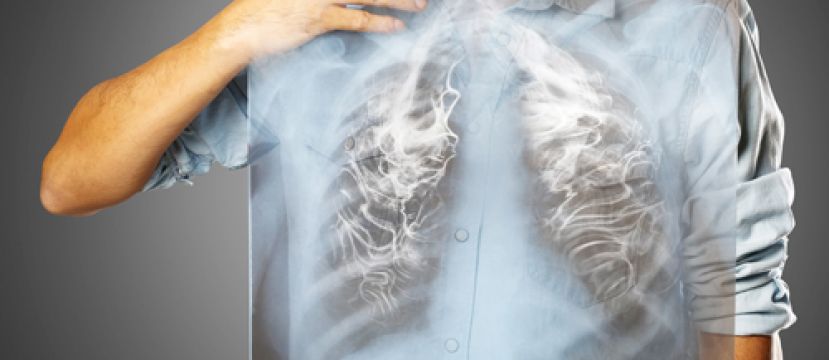

(优活健康网新闻部/综合报导)长期吸烟若年过40岁,经常有“咳、痰、闷、喘”症状要注意,可能罹患与孙越叔叔同样的疾病--慢性肺阻塞。根据卫生福利部死因统计资料显示,肺阻塞死亡为台湾十大死因排名第7位。造成慢性肺阻塞最主要危险因子就是吸烟,占所有危险因子80至90%,根据美国疾病管制局资料显示,吸烟者得到肺阻塞疾病是非吸烟者的10到13倍。

长期吸烟是肺阻塞最大危险因子

台东马偕胸腔科医师吴信宏表示,长期吸烟造成肺部屯积焦油,造成肺部慢性发炎、吸吸道狭窄不顺,造成肺阻塞。家中的抽油烟机油污多了可以换油网,但人的肺却不能换。呼吁提早戒烟远离危险因子,才是预防及治疗肺阻塞最好的方法。

诊断肺阻塞,医师会详细评估症状、吸烟习惯、是否曾暴露在危险因子,同时利用问卷评估症状的严重度。并进行肺功能检查、X光或电脑断层扫描等检查。肺功能检查是一项重要诊断检查,可测得用力呼气肺活量,利用这些数据来评估呼气气流受阻的程度。